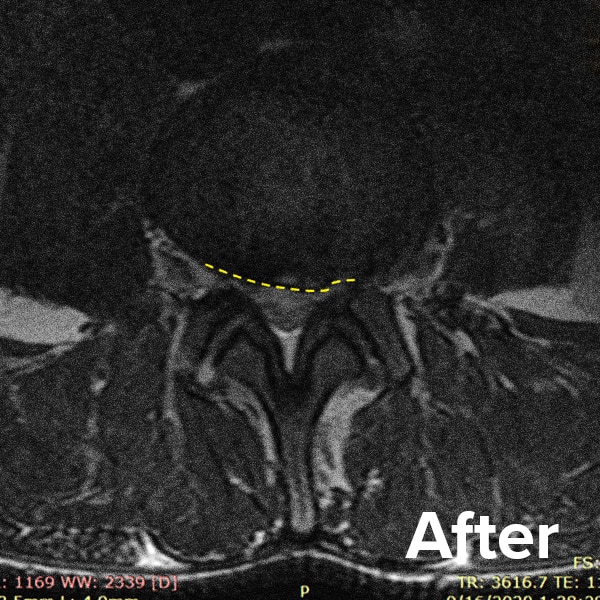

Herniated Disc MRI

Below are MRI images of the outcome of a patient who had a Regenexx PL-Disc procedure to treat a subligamentous disc herniation. After the procedure, their pain dropped quickly, and they returned to their normal activities within weeks.

Scroll the arrow to the right to see the MRI of the disc before the Regenexx PL-Disc procedure — the white/lighter area indicates damage. Scroll to the left to see the MRI of the disc after. The images are two years apart from the original treatment date.

Herniated disc before and after MRI images 2